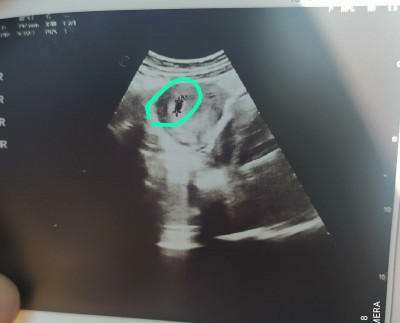

5 haftalık ultrason görüntusu bu sizce nasıl bana saçma geldi görüntü

Gebelik haftası 5 hafta

Evet canm o işaret ettiğim yer kese

Normalde yuvarlak olması lazım kese. Kurbağaya benzemiş cnm Dr ne dedi peki bunun için

Yok canım herşey normal 5 haftalık dedi bayramdan sonra kalp atışına gel

neden sacma canim bir taraftan tutup asagi dogru cubugu indirmis ortaya cikan sonuc ta kese boyutu gayet normal bende sacma bulmana sasirdim

kızmakla alakası yok sasirma sebebini anlayamadigimi soyluyorum bende senin gibi olk gebelik gecirdim benimde kesem senin gibiydi bunun ilk gebelikle 10 gebelikle.ne alakasi var herkesin kese sekli farkli toplamda 5 gebelik yasadim 1 inin kesesi.ötekini tutmuyordu onu da gectim her ay bile kese sekli degisiyor doktorun aldigi ekran goruntusuylede alakali